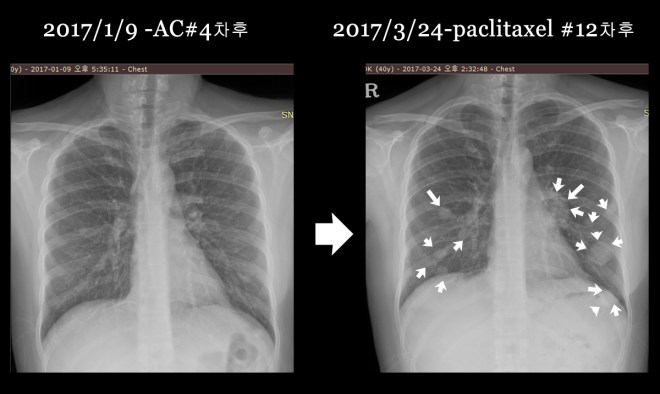

1-9.jpg

위에 보듯이 폐에 보이는 무수한 점들은 CT상에서는 더욱 선명하다. 다음에 PET에 나타나는 검은 점이나 CT상에서 동그란 솜 뭉쳐 놓은 것처럼 보이는 작은 원형의 점들이 모두 폐에 다발적으로 전이된 암을 표현한다.

서울대로 옮겨서 7 차 이후에 12 차까지 택솔을 시행하고 나서 종양이 매우 급속도로 폐에 전이가 되자 주치의는 약물을 바꾸어서 소음인 약물로만 구성된 gemcitabine하고 cisplatin을  2017년 3월부터 2017년 5월까지 시행하였다. 그리고 5월달 CT는 다소 종양의 감소를 보였다.